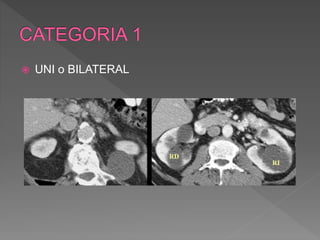

 UNI o BILATERAL

 En anomalias

congenitas

 Riñon en herradura

 Asociados a quistes de

anexos

 Menores 3cm, asintomaticas, o grandes volumenes ,

comprimen estructuras vecinas, obstruccion del sist.

Colector ,hematuria